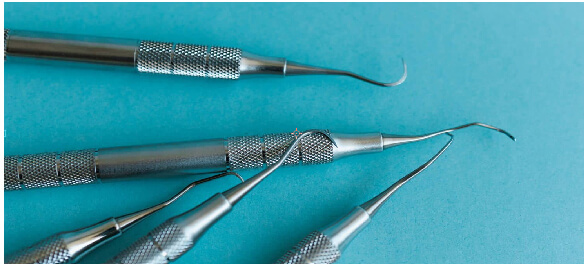

As curetas periodontais são instrumentos manuais concebidos especificamente para a remoção de cálculos subgengivais e supragengivais. Esses instrumentos são versáteis e seguros, permitindo o trabalho em áreas mais profundas sem causar danos aos tecidos moles, o que os torna a escolha ideal para tratamentos periodontais avançados, bem como para procedimentos de raspagem e alisamento radicular. O design das curetas periodontais inclui uma lâmina de trabalho com uma extremidade afiada, que possibilita a remoção eficaz do tártaro que se adere à raiz do dente. Além disso, elas contam com um cabo ergonómico que facilita o manuseamento, proporcionando maior precisão e conforto durante o procedimento.

Tipos de curetas periodontaisAs curetas periodontais estão divididas em várias categorias, cada uma concebida para um tipo específico de tratamento e acesso a diferentes áreas da dentição: